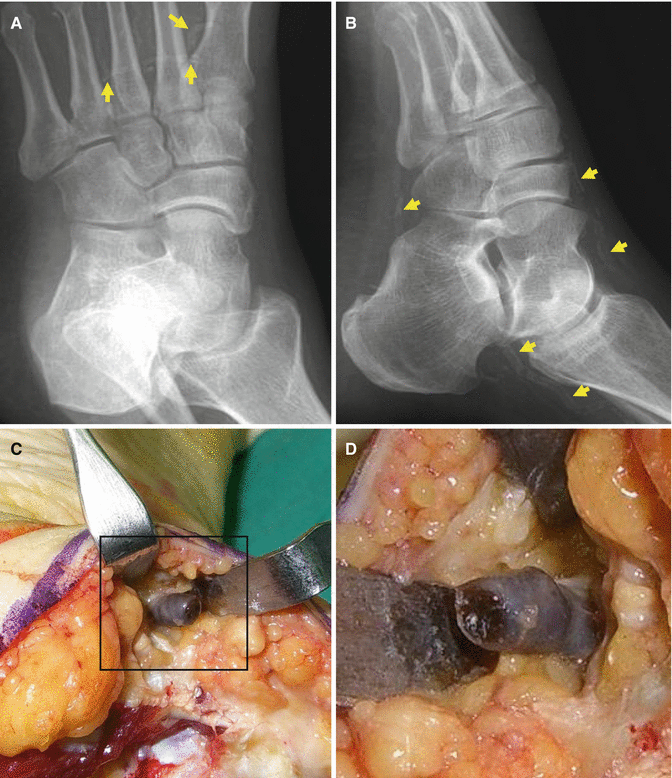

Fig. 6.1

Occlusion of the arteries distributed in the ankle joint due to atherosclerosis and blood debris in patients with diabetic feet. (A, B) Blood vessels are visualized even on plain X-ray due to calcification of the debris in the blood vessels (arrows). (C) Gross finding of the occluded vessel. (D) Close-up view